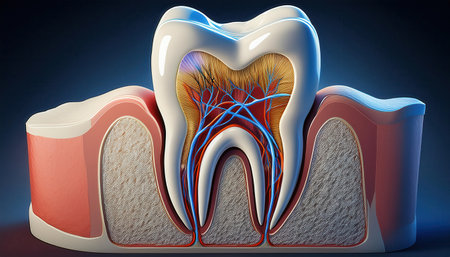

A stunning dental model showcases the elegance of stomatology in a serene setting.

A close-up view of an anatomical model of a human molar tooth's cross-section. The white enamel cap transitions to yellow dentin, revealing the red pulp chamber and root canals within. The surrounding bone structure is depicted with porous texture in beige and red hues. The background is a solid, deep blue.

Detailed depiction of a tooths anatomy highlighting its internal structure and layers.

Tooth model displaying its complex internal structure including enamel, dentin, pulp, and root canals, standing against a vibrant background of colorful, out of focus lights

This image presents a detailed anatomical model of a human tooth, highlighting its layers in a contemporary dental environment for educational purposes.

Dental tooth cross section model showing enamel, dentin, pulp, gum and root structures against a soft colorful bokeh background for oral health education and dentistry study

A detailed dental model illustrates the anatomy of a human tooth highlighting its inner structure including roots and nerves. This model is used for educational purposes in a dental clinic.

This image depicts a detailed anatomical model of a human tooth, showcasing the intricate internal structures, including nerves and blood vessels, essential for educational and healthcare purposes.

Teaching model of a tooth in cross section, close-up

Human tooth anatomy model in dental laboratory. 3d render illustration.

A detailed dental model displaying two human teeth, emphasizing the enamel and root structure. Ideal for education and professional use in dental practices.

Human tooth cross section. 3d illustration

This image provides a detailed cross-section view of a human tooth, revealing the inner anatomy including the root pulp and surrounding bone structures. It is an educational and informative visual aid

Detailed cross-section of a human tooth displaying enamel, dentin, pulp, and root anatomy. Educational medical illustration on a gradient blue background.